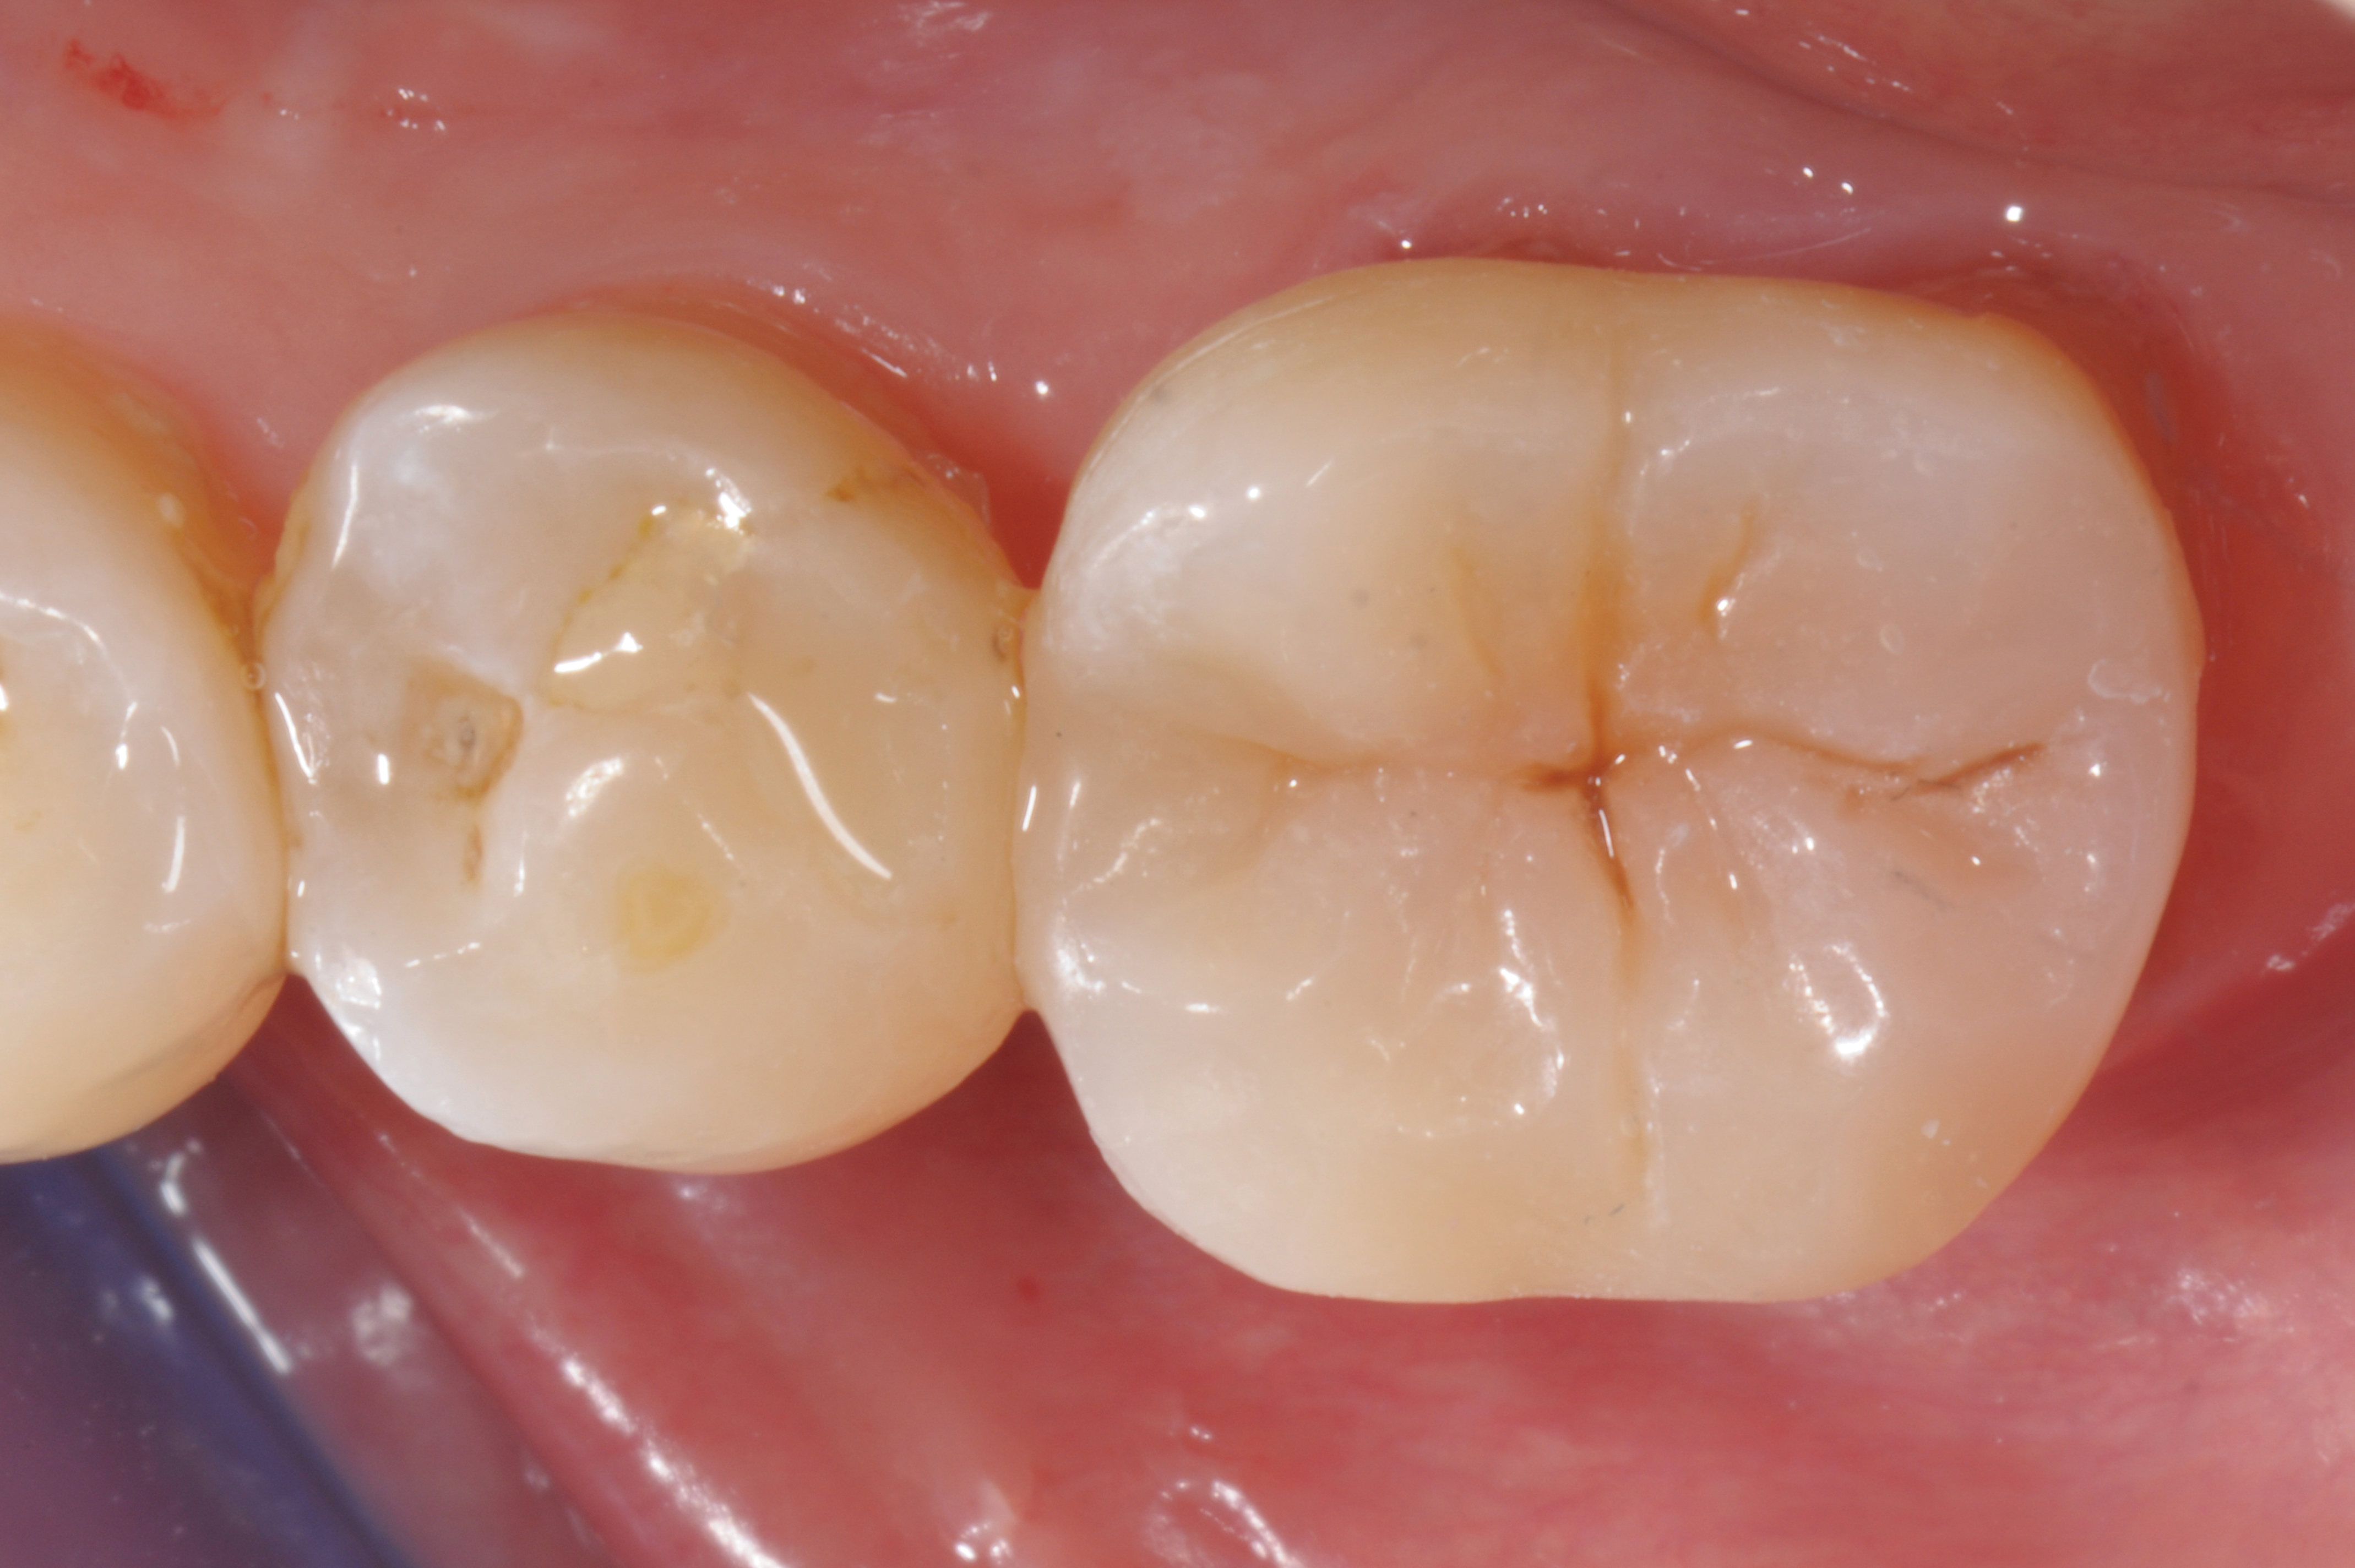

When following a protocol of cementation using an adhesive system, constant rubber dam isolation and careful hand finishing are necessary to provide predictable clinical results (Figure 1 through Figure 4).2

Fig 1. A mandibular first molar, with a fractured composite restoration: cavity preparation.

Figure 1

Fig 4. Postoperative view.

Figure 4